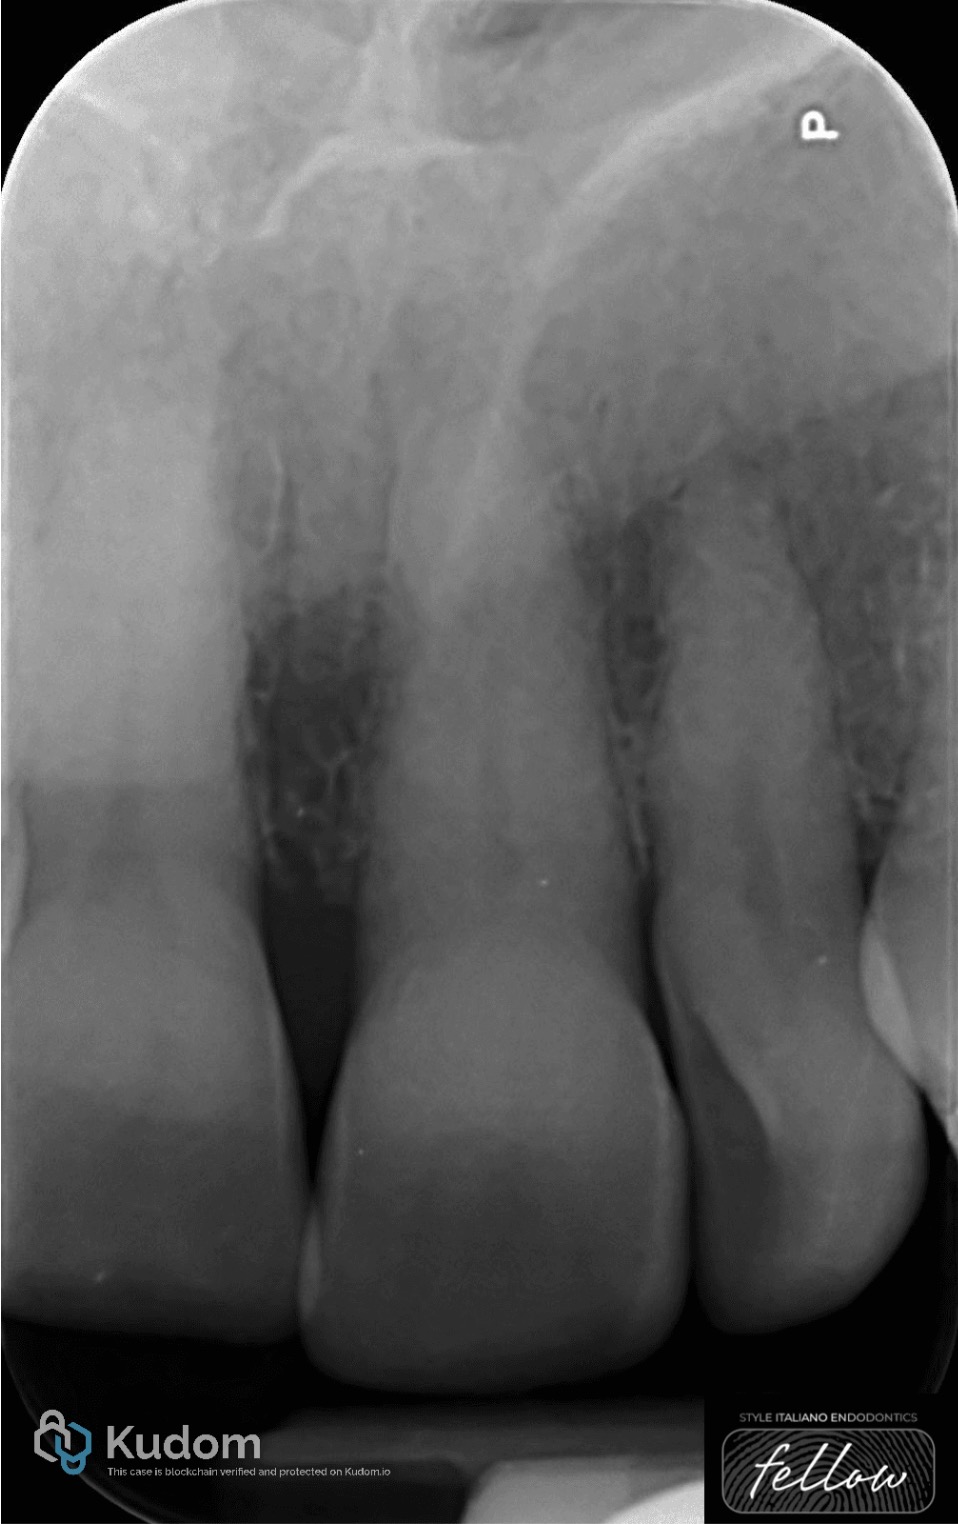

A 2-mm vetroionomer barrier was positioned over the gutta-percha to establish a cervical seal. Subsequently, a 35% hydrogen peroxide bleaching gel was applied within the pulp chamber and left in place for a duration of seven days.

Fig. 4